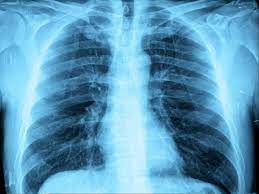

- It originates from distinctive white patches on chest X-rays in affected children.

- The term includes various respiratory illnesses like acute respiratory distress syndrome, pulmonary alveolar microlithiasis, and silica-related conditions.